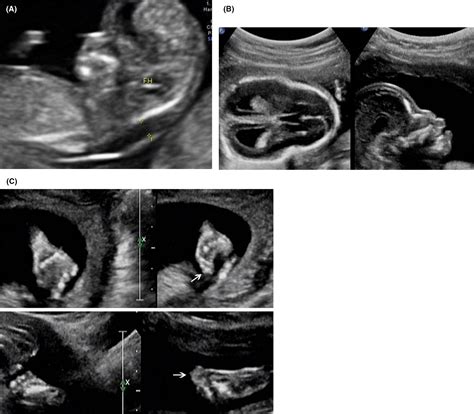

The identification of Pfeiffer Type 2 usually occurs during the neonatal period due to its distinct physical presentation. The hallmark of this condition is the "cloverleaf skull" (kleeblattschädel) deformity, which is caused by the tri-lobular shape of the cranium resulting from multi-suture craniosynostosis.

Unlike Type 1, which may present with milder symptoms, Pfeiffer Type 2 involves a more aggressive progression of cranial anomalies. The fusion of these bones forces the skull to grow in abnormal shapes, often leading to increased intracranial pressure. This creates a cascade of physiological challenges that extend well beyond cosmetic concerns, affecting neurological function and overall development.